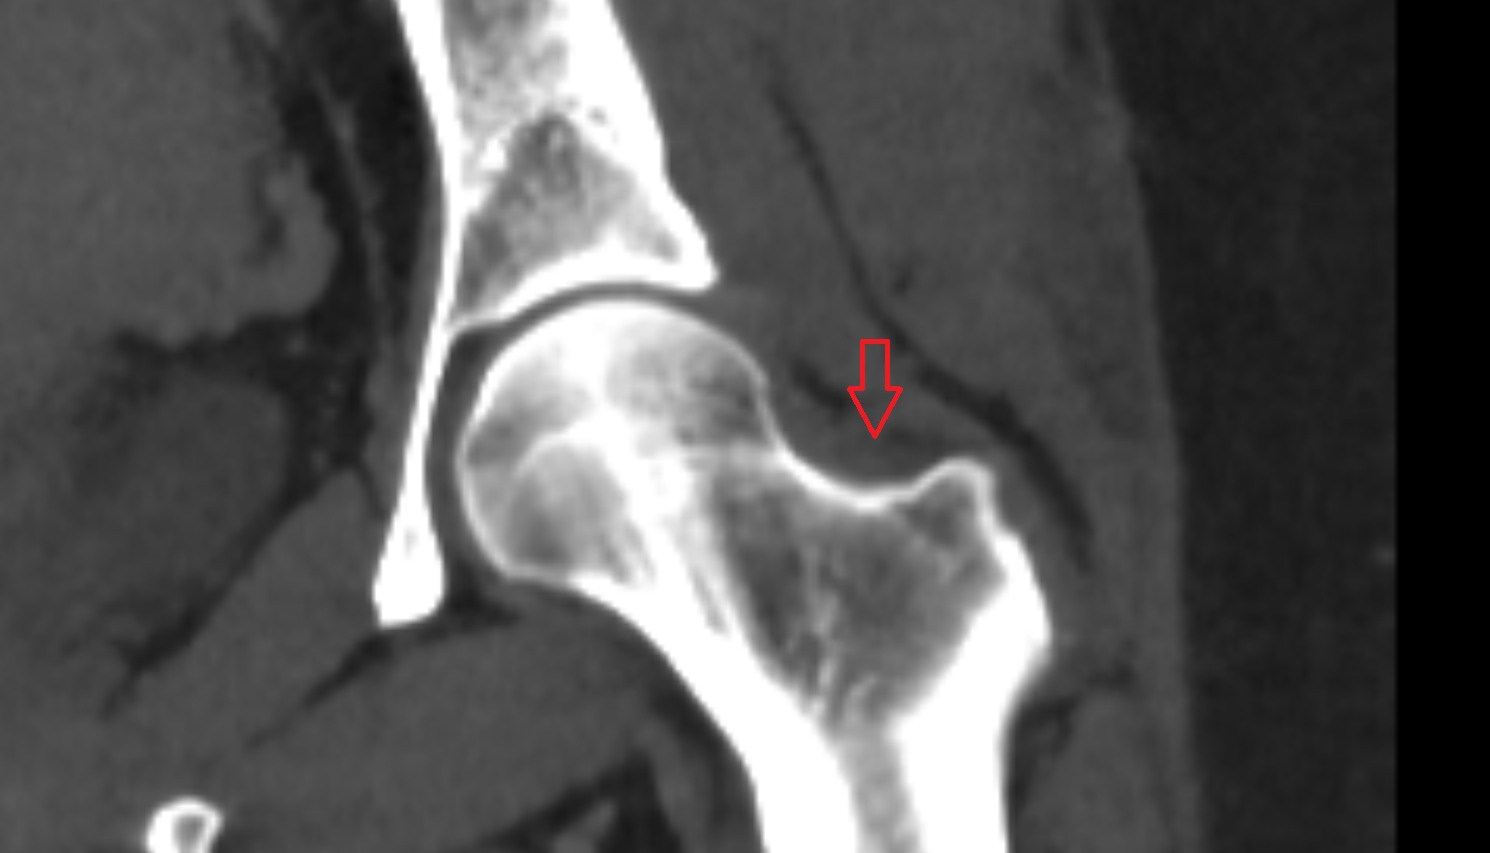

- Head of femur

- Neck of femur

- Greater trochanter

- Acetabulum

- Hip joint